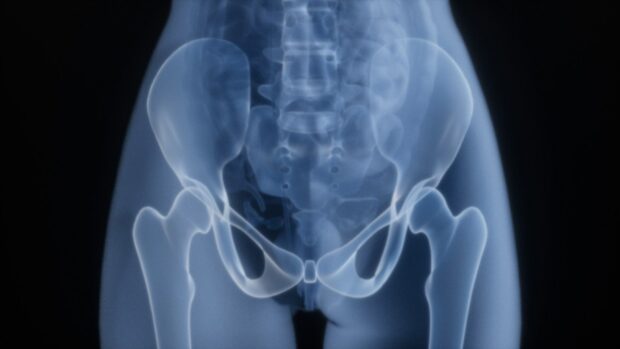

Older women who reported drinking tea had higher-than-average hip bone mineral density (BMD) in a 10-year study involving thousands of women in the United States. The study from a...